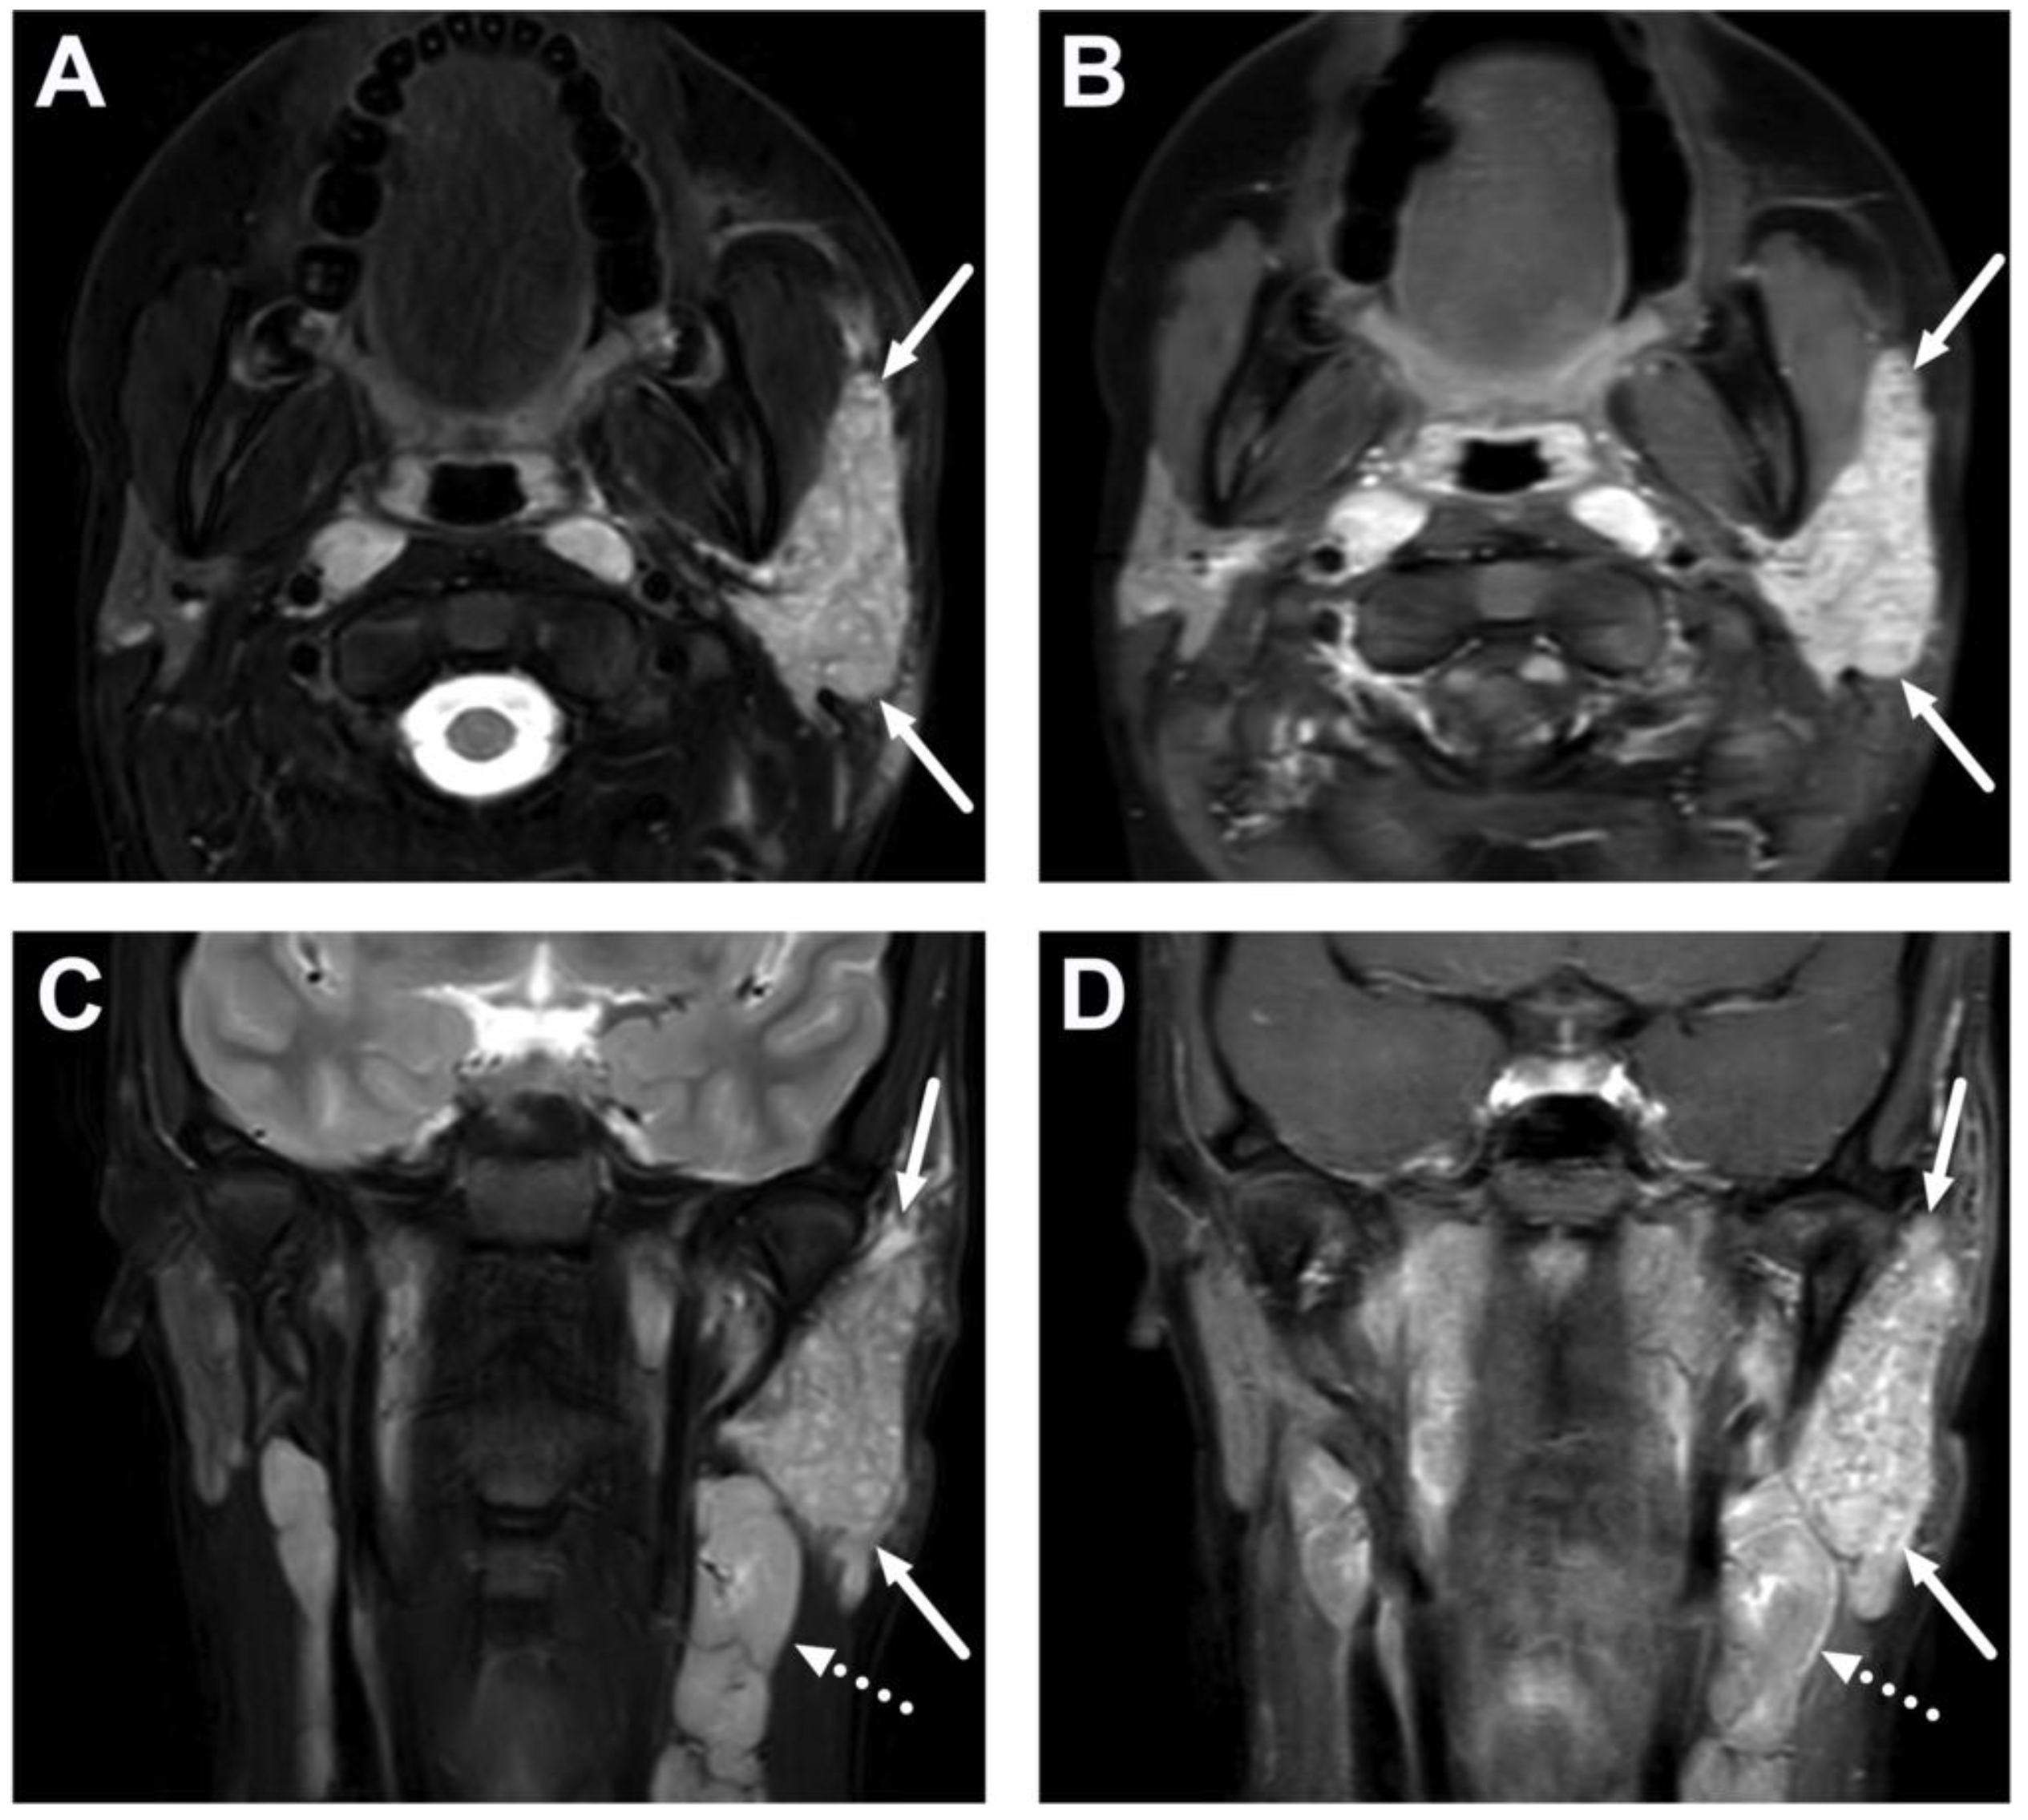

6. Complications

6.1. Mediastinitis

| Abscess | T1 SE T2 Dixon (water) DWI post-contrast T1 Dixon (water) | Non-enhancing collection with low ADC values enclosed in abnormally enhancing soft tissue edema. | Detection of an abscess usually requires operative consideration and exact abscess location, and extensions are useful in operative planning. | Abscesses may have an intermediate T2 signal content; blood products and/or postoperative status may complicate abscess assessment; necrotic lymph nodes may be misinterpreted as suppurative lymphadenitis. |

| Complications | Whole protocol | Abscess extending to multiple deep neck spaces, mediastinis, venous thrombosis, and airway compromise. | Detection of potentially life-threatening conditions. | Magnetic resonance angiography (MRA) or CECT may be needed to diagnose venous thrombosis; defining airway compromise is difficult. |